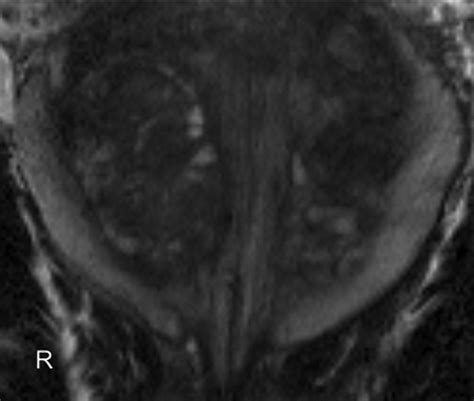

• Multiparametric MRI (mpMRI): This technique combines multiple MRI sequences, including T2-weighted imaging, diffusion-weighted imaging (DWI), and dynamic contrast-enhanced (DCE) imaging, to provide a comprehensive evaluation of the prostate.

• Fusion Biopsy: This technique combines MRI images with real-time ultrasound guidance to perform targeted biopsies, improving the accuracy of cancer detection.